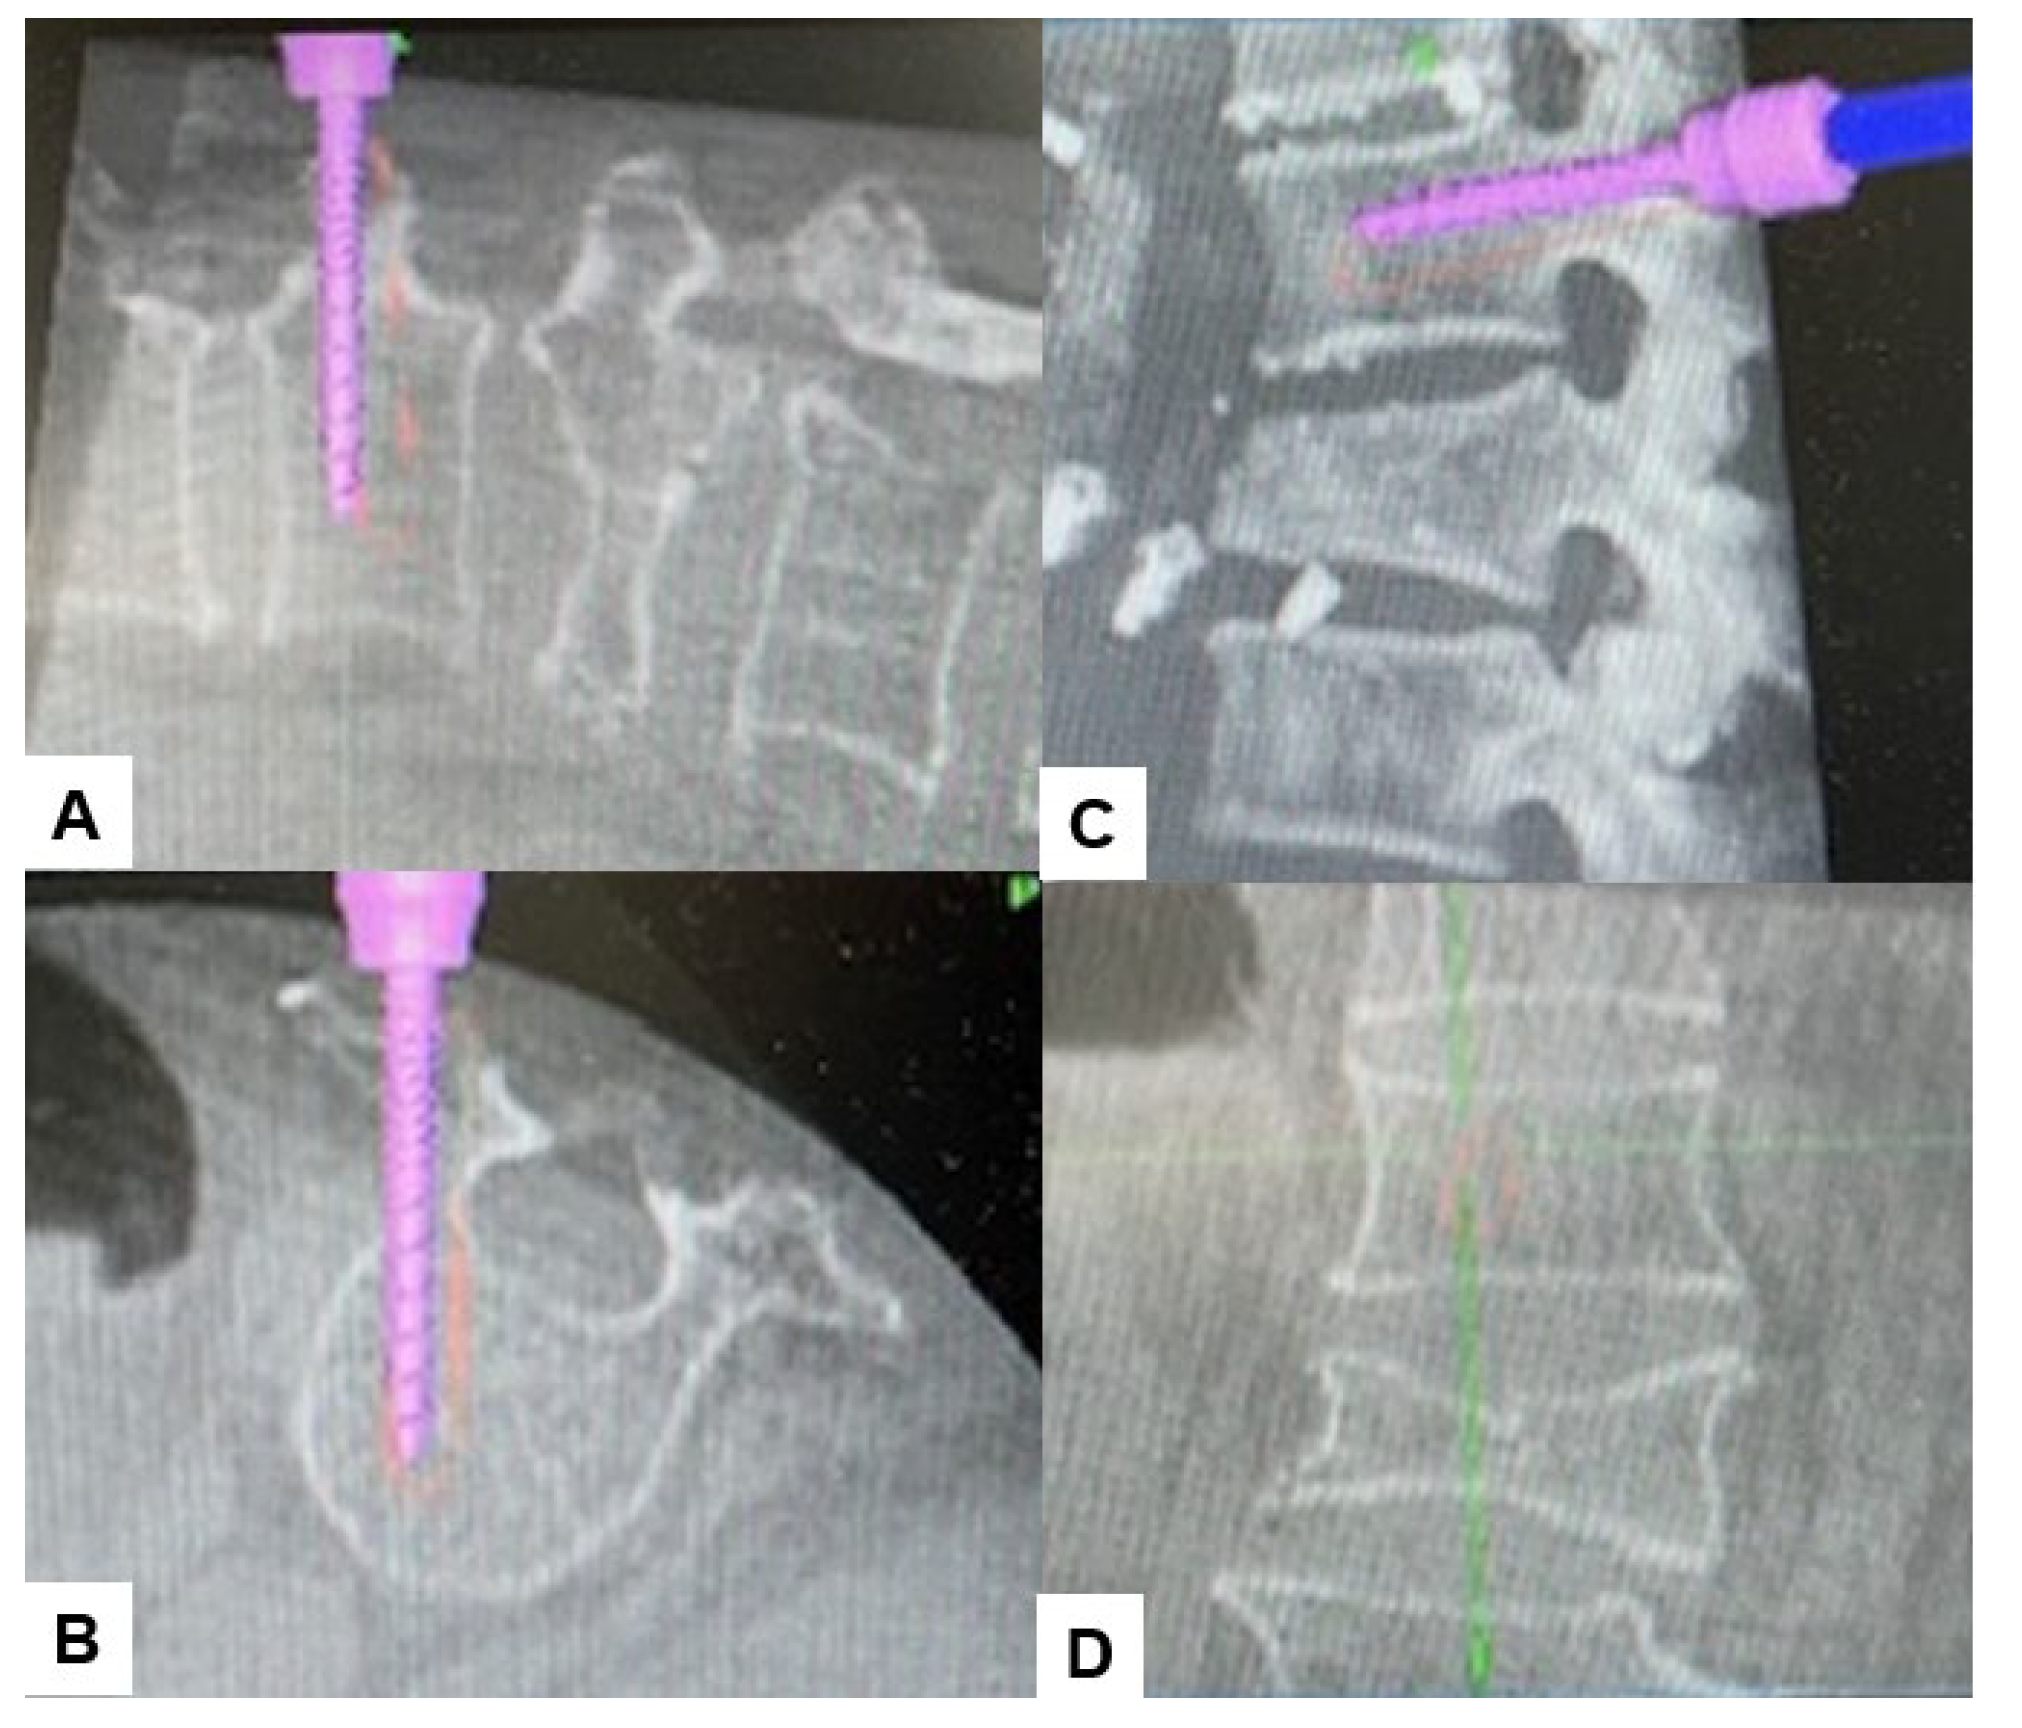

2.4. Surgery